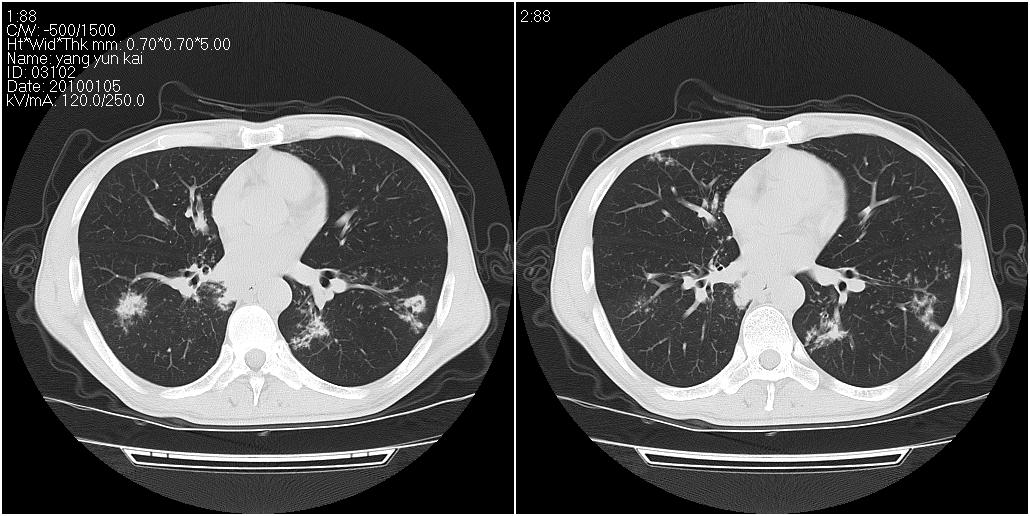

标题: CT23980:男性,47岁。近来咳痰、咳血,血沉增快(40左右),

男性,47岁。近来咳痰、咳血,血沉增快(40左右),痰中未检出结核杆菌。

两肺继发性肺结核并多发性结核球形成,部分病灶内空洞形成。